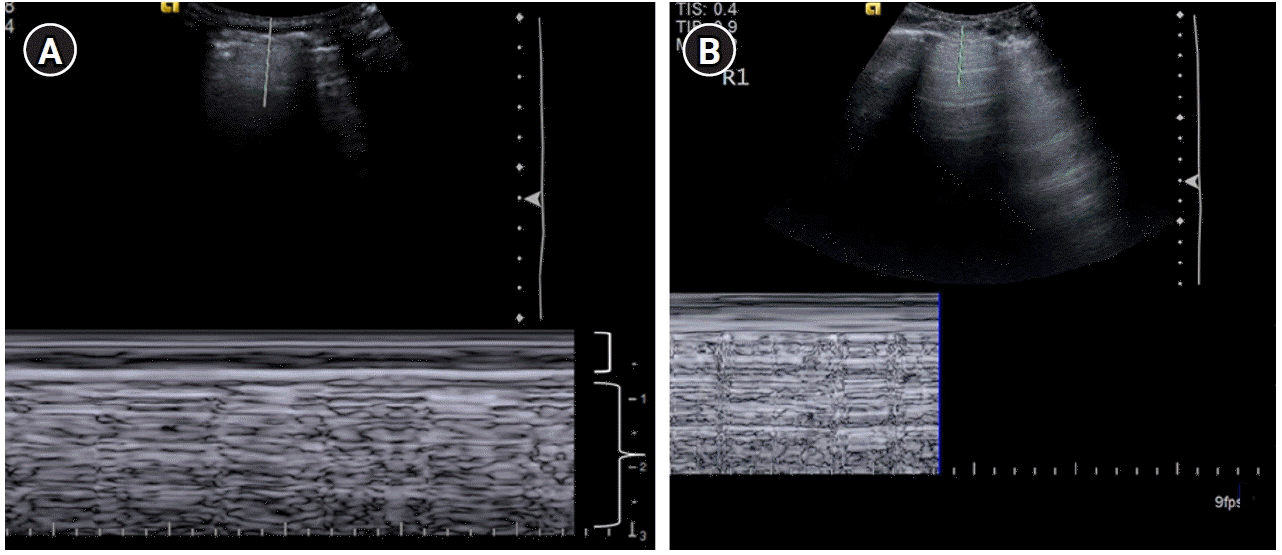

Figure 5.

Lung sliding. (A) M-mode with the cursor over the pleural line illustrating the “seashore sign.” The motionless portion of the chest above the pleural line creates horizontal “waves,” (bracket) and the lung sliding below the pleural line creates a granular pattern, the “sand” (brace). (B) Cine US clip demonstrating the same (Supplementary Material 2).